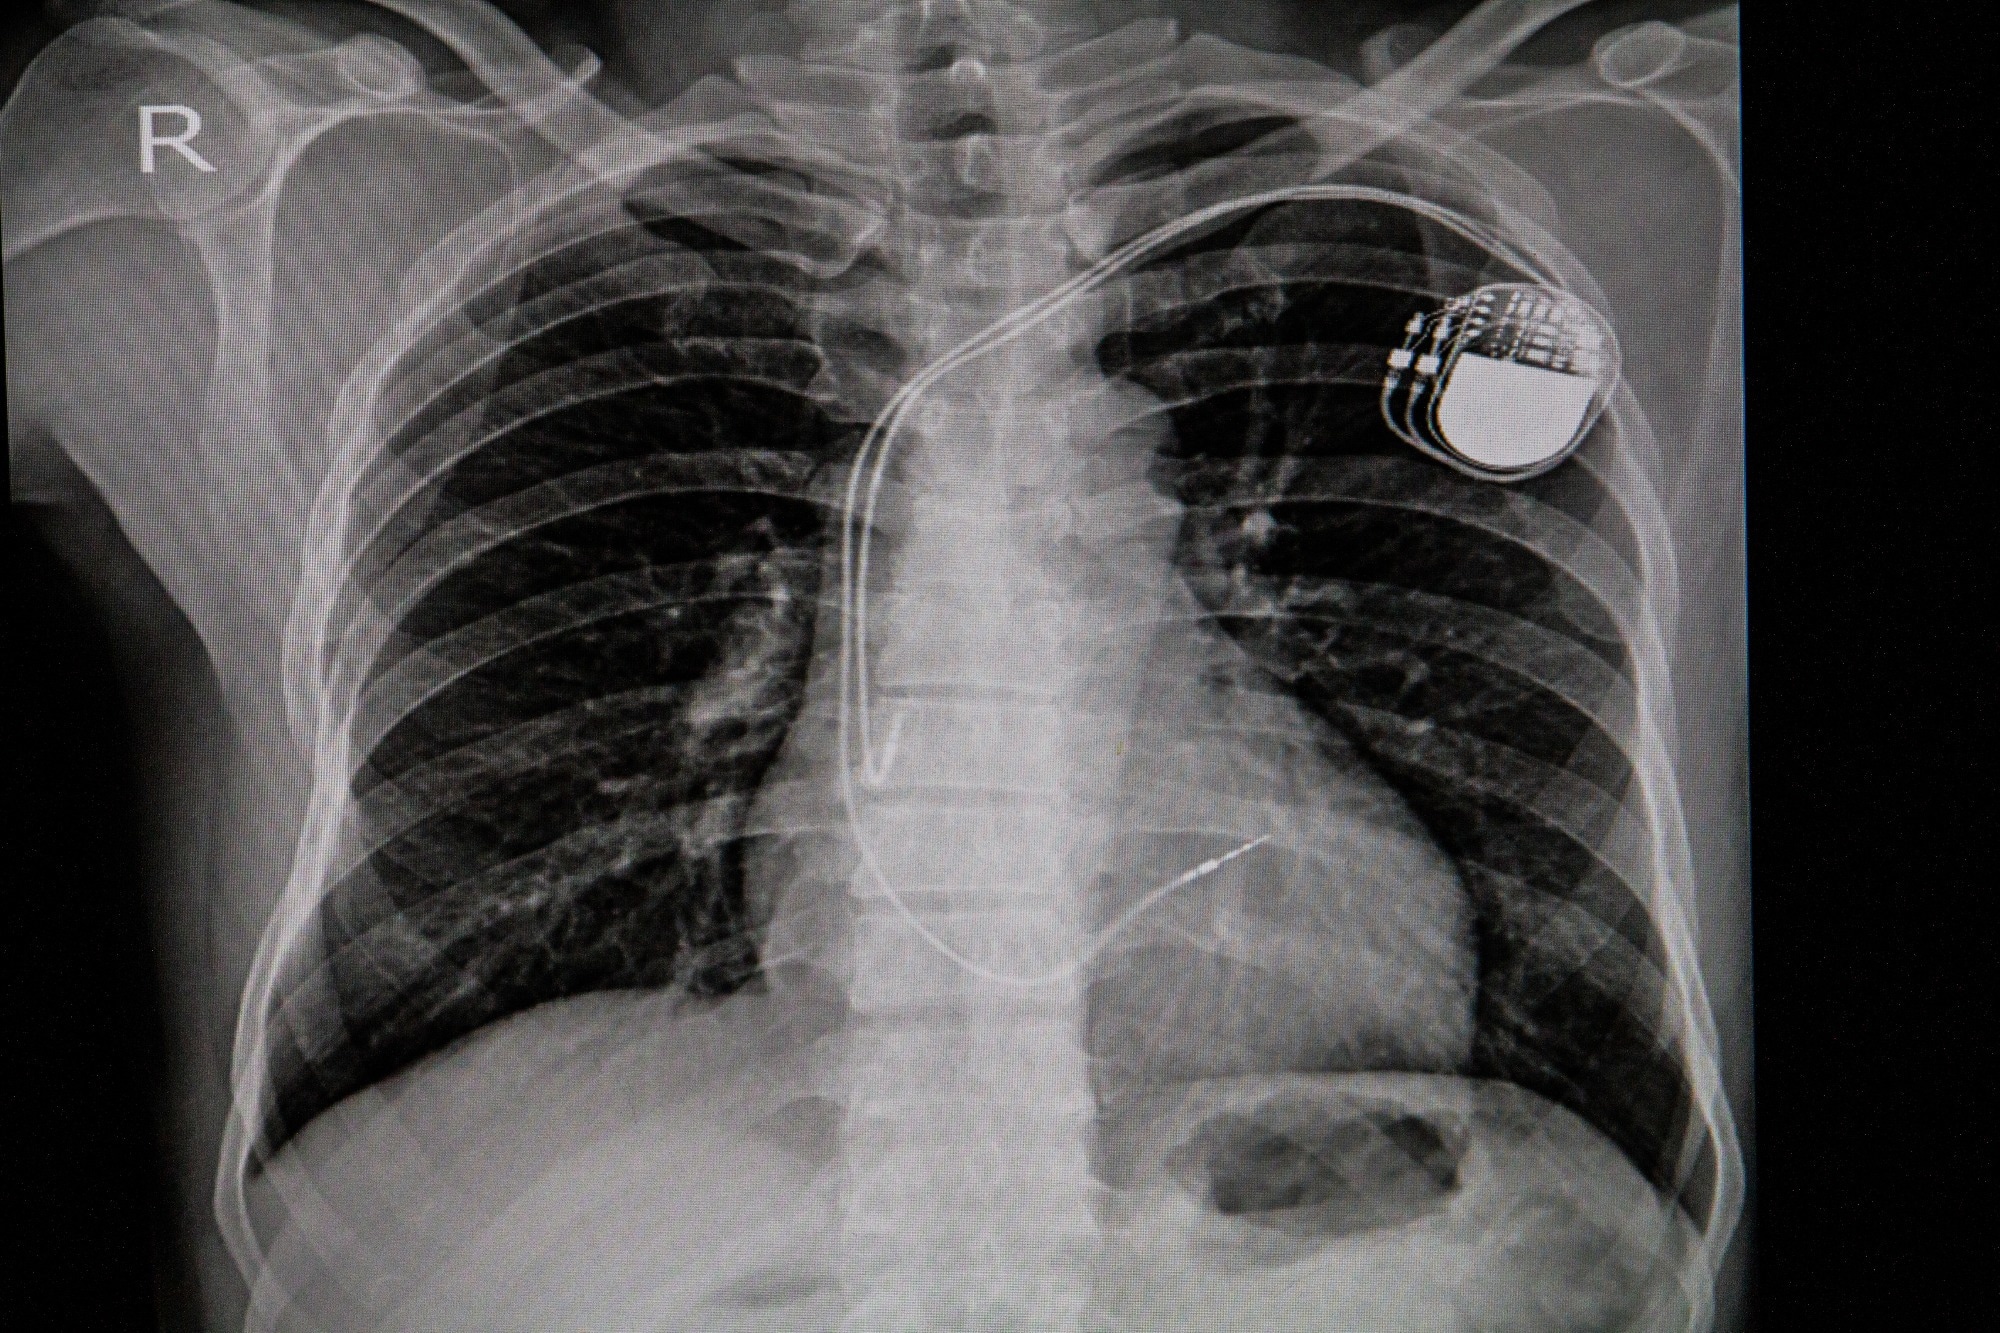

Study: Generative Artificial Intelligence for Chest Radiograph Interpretation in the Emergency Department. Image Credit: April stock / ShutterstockStudy: Generative Artificial Intelligence for Chest Radiograph Interpretation in the Emergency Department. Image Credit: April stock / Shutterstock